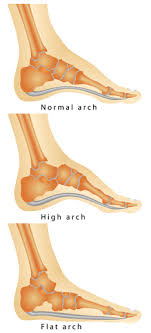

The VA awards disability compensation for injuries to the Foot and Lower Leg Muscles that are service-connectedThe DoD will also rate service-connected muscle injuries as long as they also make the service member Unfit for DutyFor Reservists the injury must have occurred in the Line of Duty to qualify. The VA rates flat feet as per the 38 CFR 471a Schedule of Ratings Musculoskeletal System with the diagnostic code 5276. Cant find in the cfr the criteria for rating flat feet percentages. Moderate flat feet is when a veterans weight-bearing line is over the medial great toe there is inward bowing of the Achilles tendon and pain on manipulation and use of the feet.

The VA determines a pes planus rating depending on the severity of the injury. Veterans with severe bilateral flat feet can receive a disability rating of 30. To summarize if your feet are as flat as Katy Perrys singing and just as painful you may be able to get 50. It is essential to make an initial distinction between bilateral flatfoot as a congenital or as an acquired condition.

If severe and there is suspicion of major tendon or soft tissue damage an MRI may be performed. Currently Veterans can receive a rating between 0 and 50 percent for pes planus. Through the rating criteria in this code the VA will evaluate your symptoms and give you a rating on a scale of 0 mild disability to 50 pronounced disability. Relationship Between Flat Feet Pes Planus and Veterans.

Pes planus among veterans can be caused by a variety of factors. For Reservists the condition must have occurred in or resulted from an injury in the Line of Duty to qualify. And use of the feet. Veterans with severe bilateral flat feet can be rated at 30 percent.